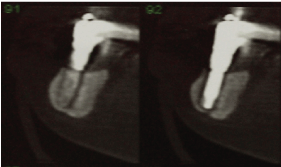

访问期间,增加成交量中观察到的后区右侧下颌骨和流动性在该地区的最末端的植入物,它是不可能的诊断是否产生的流动性被植入或下颌骨折(图1)。图像检查后,在皮瓣嵴处观察到一条透光线,一直延伸到种植体基底处,这表明下颌骨骨折无碎片脱离。我们还可以观察到,这是一个骨高度小的下颌骨,除了一个外,其他种植体显示边缘骨丢失(图2和3)。

图3:远端种植体的断层,可以确认下颌骨骨折而不脱离。